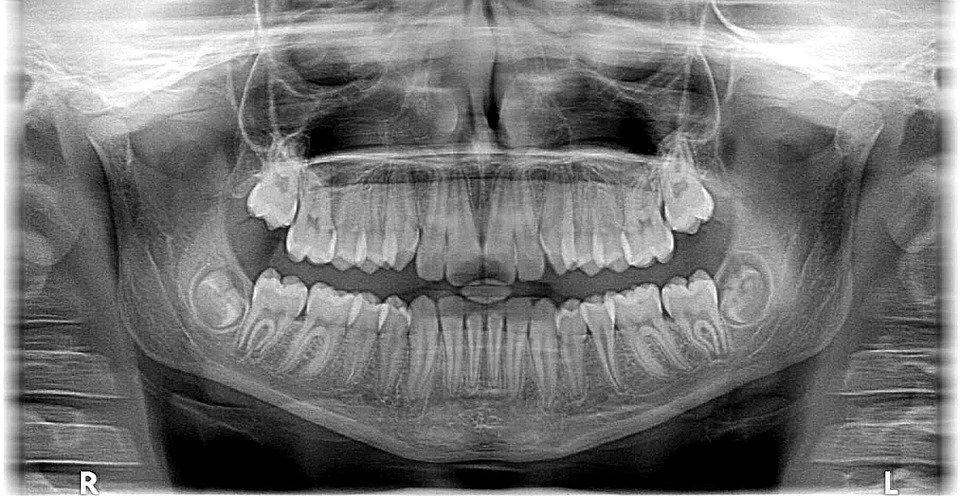

Dental CT scans reveal the truth of your teeth

For accuracy, your dentist will take multiple X-rays and, if necessary, a few CT scans as well. Your dentist may even want your medical history to account for any chronic or previous conditions. And if he or she discovers anything worrisome, your dentist may even consult your family doctor to learn more about how your body responds to treatment.

From there, your dentist will decide where to place the implants to best support new teeth and to reinforce the remaining bone. He or she will also assess the quality and quantity of your bone, and your dentist may recommend an additional bone graft to avoid complications.